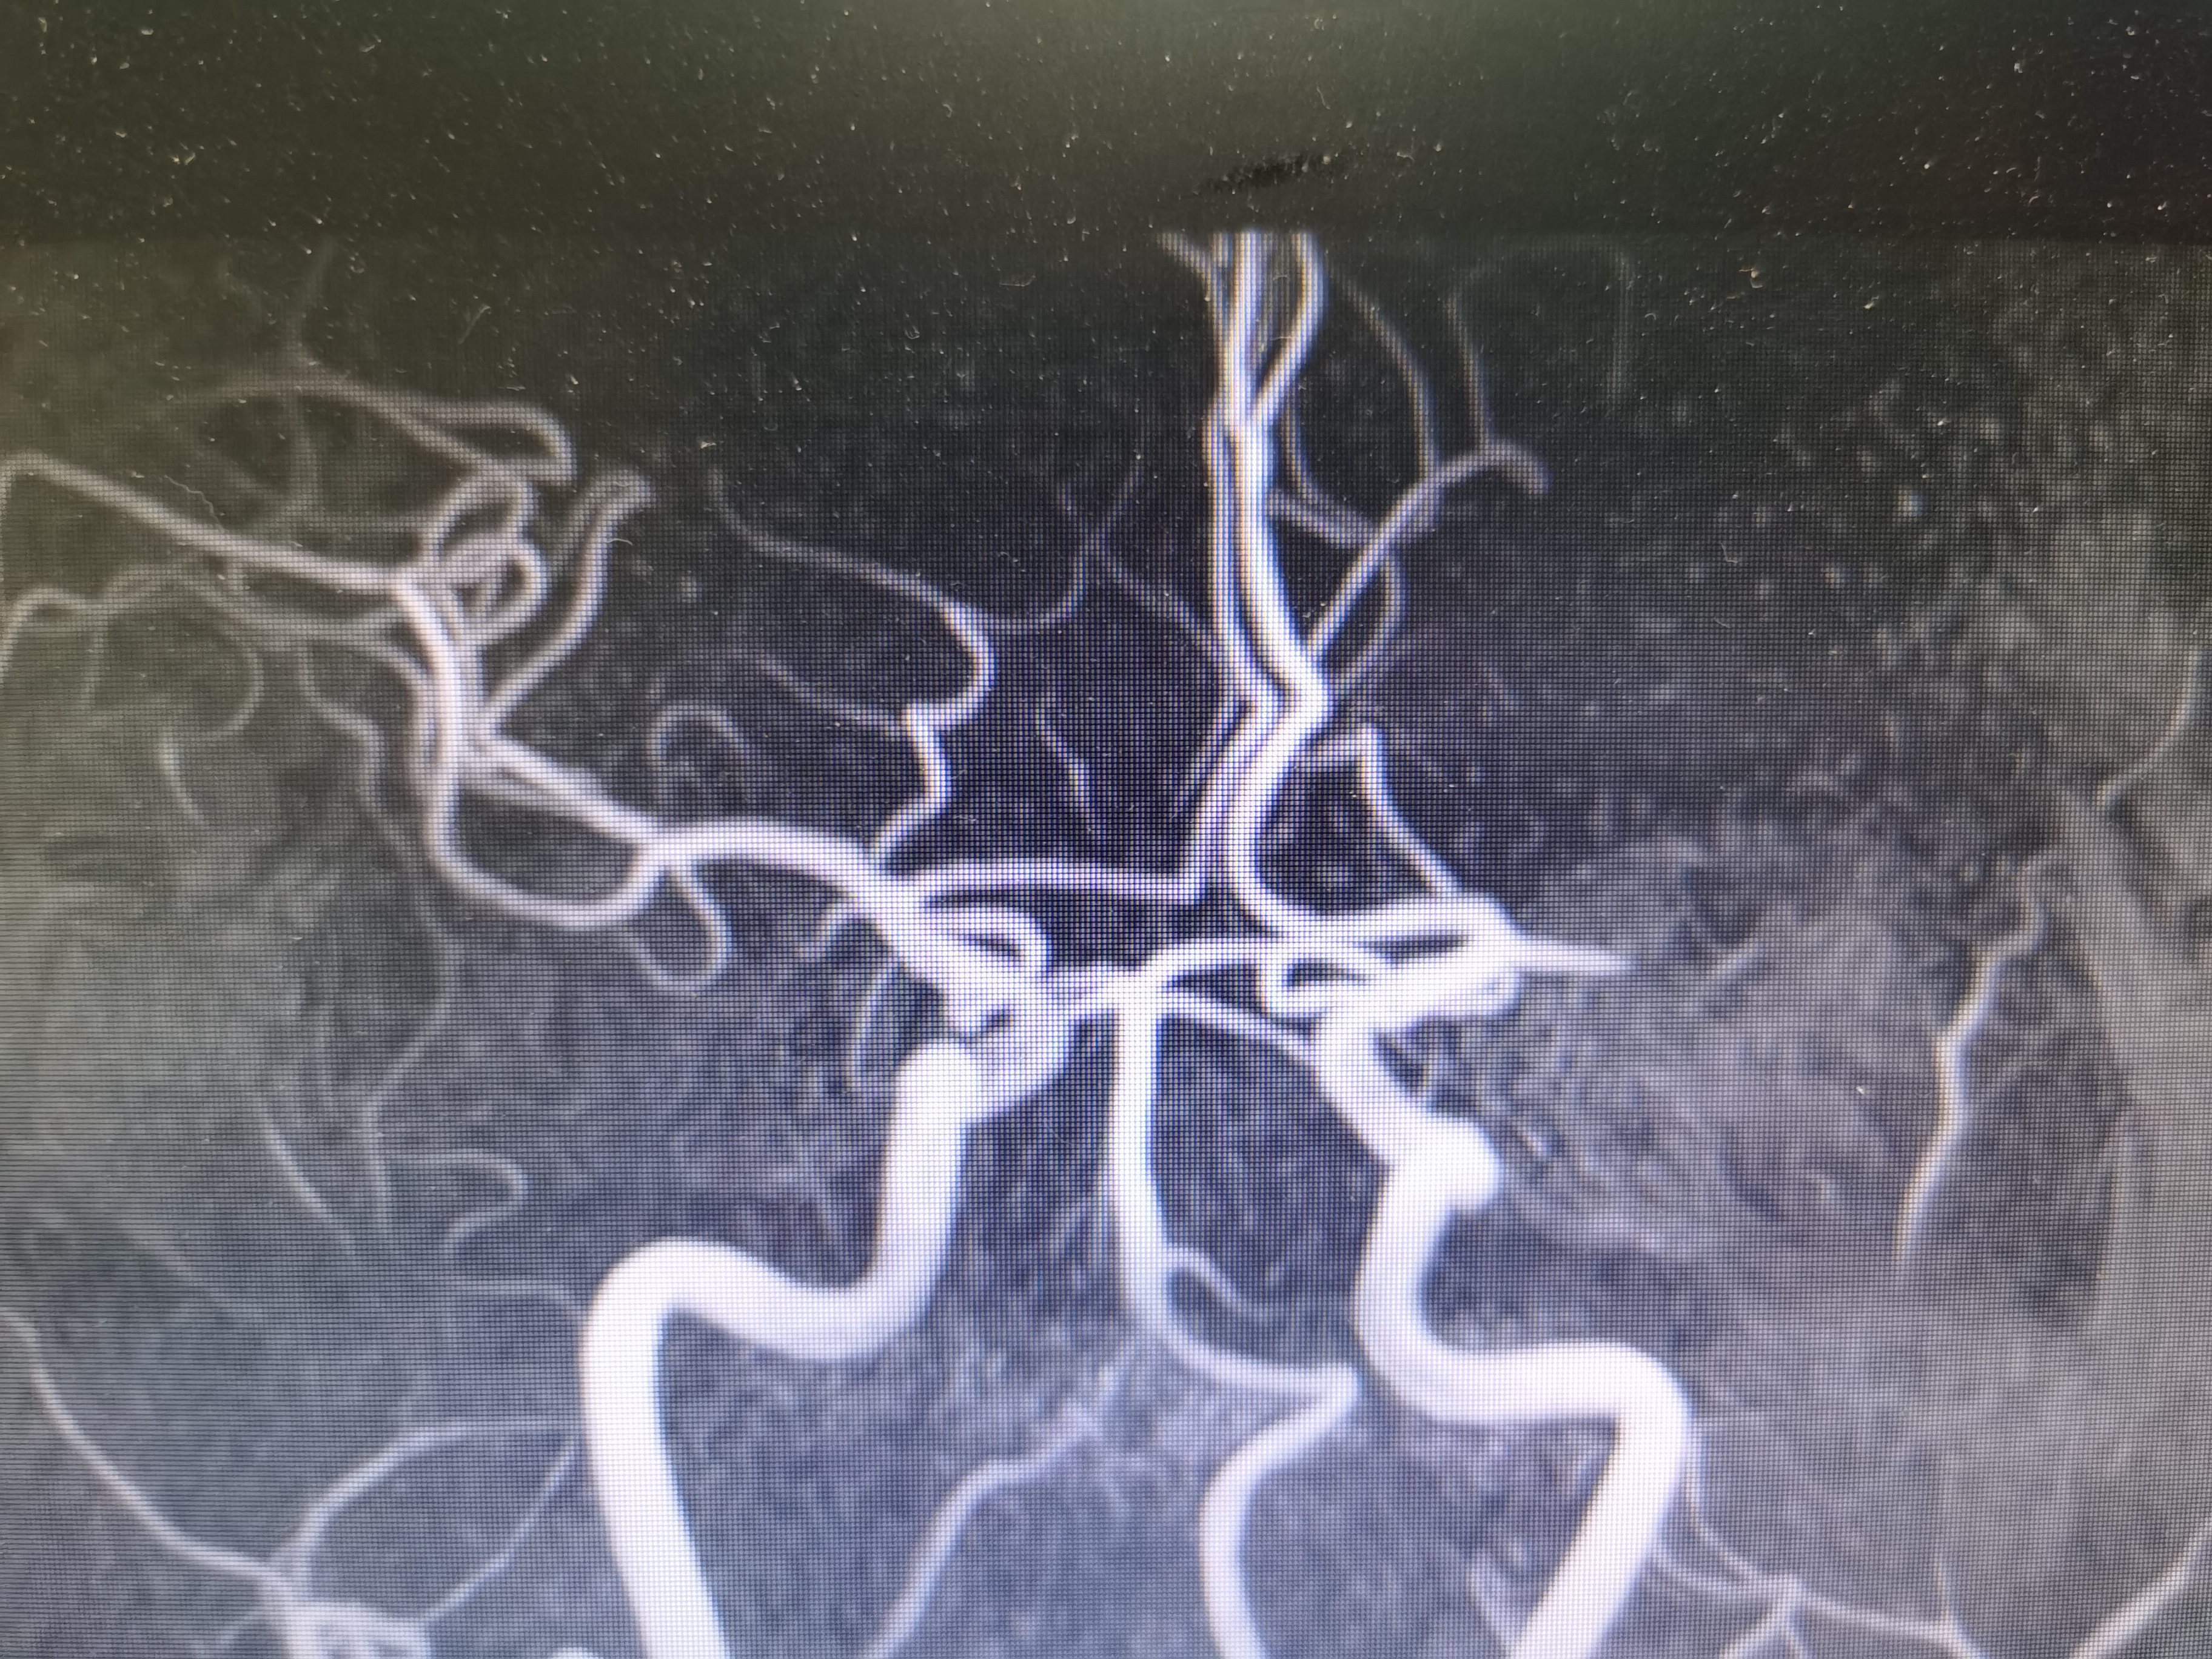

MRA示左侧大脑中动脉闭塞。

患者中年男性,被发现言语不利,右侧肢体无力,具体发病时间不详,经核磁评估提示左侧大脑中动脉闭塞导致左侧半球大面积低灌注梗死,具备介入治疗指征。紧急联系家属沟通后行脑血管造影评估备血管内治疗。